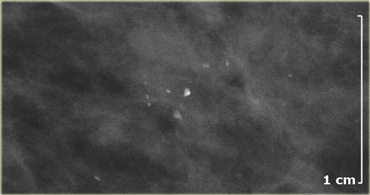

The calcifications on the left were detected on the first mammogram in a screening program.

There is a cluster of amorphous and fine pleomorphic calcifications.

These calcifications were classified as BI-RADS 4B.

A biopsy was performed and only fibrocystic changes were found.

On the left a case that looks quite similar to the one above.

New calcifications were detected during follow up in a screening program.

These are fine pleomorphic calcifications in a cluster.

These calcifications were classified as Bi-RADS 4.

This proved to be DCIS.

The message is that with these calcifications you cannot tell whether they are malignant or not and they have to be biopsied.